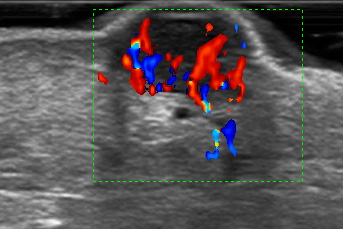

Ecografia Doppler de Partes Blandas

Permite evaluar masas, inflamaciones o infecciones en músculos y tejidos, observando además el flujo sanguíneo con Doppler para obtener un diagnóstico más preciso.